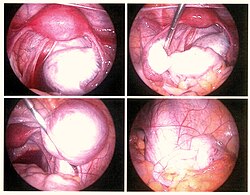

Cərrahiyyə müalicəsi

Endometriozun (düyünlərin) hər hansı bir cərrahi üsulla tamamilə çıxarılması nəzərdə tutulur. Hal-hazırda rezeksiya, elektrokoaqulyasiya, lazer buxarlanması istifadə olunur. Onların hamısının effektliyi sübut edilmişdir, lakin heç birinin digərlərindən əhəmiyyətli üstünlüyü tapılmamışdır.

Bir çox cərrahlar hesab edirlər ki, rezeksiya bütün düyünləri, xüsusən buxarlanma və ya elektrokoaqulyasiyadan sonra tamamilə yox ola bilməyən böyük düyünləri daha yaxşı çıxarmağa imkan verir. Bu üsul eyni zamanda biopsiya üçün material götürməyə imkan verir.

Endometrioid yumurtalıq kistlərinin tam çıxarılırması ən uyğundur. Əməliyyatdan sonra bu üsulun üstün olduğu sübut edilir və nadir yumurtalıq şişlərini istisna etmək üçün histoloji müayinə üçün materialı vaxtında götürməyə imkan verir.